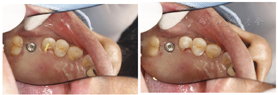

临床检查见26残根占位,牙槽嵴丰满度一般,龈合距离与近远中间隙基本正常,表面黏膜光滑,无扪痛(图1)。CT显示:残根存,26可利用牙槽嵴高度约2 mm。

26残根